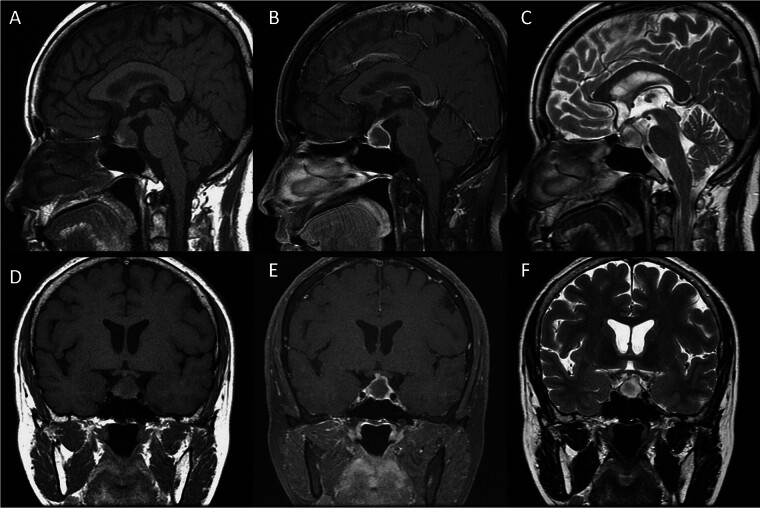

Case presentation: A 60-year-old woman with having medical history of diabetes mellitus who suffered from severe headache, fever, chillness, and vomiting in January 2024. She had been admitted to the Infectious Diseases Department; however, no definite infection source was found, but hypopituitarism was detected. Her brain magnetic resonance imaging (MRI) showed a rim-like enhanced sellar lesion with suprasellar extension. She underwent an endoscopic endonasal transsphenoidal approach with the removal of the lesion and skull base reconstruction. During the surgery, pus-like material and some solid tissue, which was yellowish white in color, were found. The culture of the pus revealed the growth of Cutibacterium acnes, and the histological report of the solid tissue proved nonneoplastic pituitary gland tissue, admixed with fibrous tissue and marked chronic inflammation. She recovered well after surgery and completed antibiotic treatment.